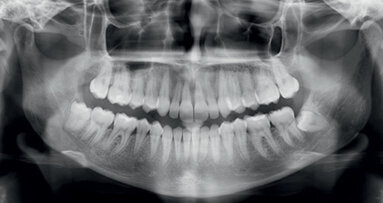

Jednou jsem se zeptal mého dobrého přítele, Yoshiho Terauchiho, kolik kanálků opracuje s jedním nástrojem, než ho vyřadí a začne pracovat s nástrojem novým. Odpověděl: „Používám rotační instrumenty do jejich zlomení, odstraním ulomený fragment a pokračuji s novým nástrojem.“

Cože!?“ pomyslel jsem si a díval se na něj, jako by měl dvě hlavy. Šokovalo mě to, protože každý den, kdy se objeví „syndrom krátkého nástroje”, je velmi špatný den v životě všech zubařů, kteří provádí ošetření kořenových kanálků. Skepticky jsem se ho zeptal, jak tohle může říct s vážnou tváří a řekl, že mu trvá jenom 1–5 minut odstranit z kořenového kanálku všechny fragmenty.

Tudíž jsem od Yoshiho slyšel dva na první pohled směšné názory: První, že se nebojí zlomení nástroje, a druhý, že považuje odstranění zlomených nástrojů za prediktabilní proceduru, která vyžaduje relativně málo času. SKUTEČNĚ? Naštěstí znám Yoshiho mnoho let, tak jsem fatální vyjádření nedůvěry k těmto prohlášením ještě zadržel a zeptal se ho na vysvětlení. To, co mi odvětil, převrátilo na ruby vše, co jsem dosud údajně věděl o odstraňování zlomených nástrojů. Tyto oblíbené mýty zahrnovaly:

Následují zásadní tvrzení o odstraňování fragmentů nástrojů – mnohé z nich definované Dr. Yoshi Terauchi, který také sestavil Terauchi File Retrieval Kit (TFRK), k provádění této v minulosti náročné a nepředvídatelné procedury (obr. 1).